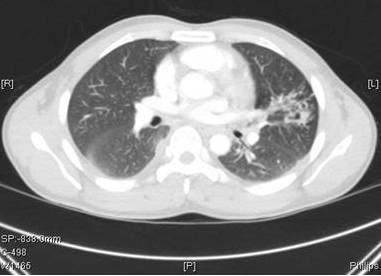

图1就诊前4个月的胸部CT

图2: 出现症状是的胸部CT(进行4个月的抗结核治疗)

肺吸虫囊肿通过BAL和支气管镜活检证实。

与肺结核相反,肺吸虫病很少伴有啰音或偶发呼吸音。急性期(侵袭和转移)可表现为腹泻、腹痛、发热、咳嗽、荨麻疹、肝脾肿大、肺部异常,外周和BAL样本中嗜酸性粒细胞增多。肺吸虫侵袭和迁移的时期的急性期包括腹痛、腹泻和荨麻疹,随后大约1到2周后出现发热、胸膜炎性胸痛、咳嗽和/或呼吸困难。在慢性期,肺部症状较轻,并有咳嗽、咯血痰,痰液变色,和胸片异常。影像学异常包括胸腔积液、局灶性纤维化胸膜增厚、胸膜下结节,实质性团块,迁移性浸润、空洞性病变、印戒征,少见气液平。最常见的有症状的肺外部位是中枢神经系统。大脑中的吸虫可导致剧烈头痛、头晕、视力障碍。慢性感染可表现为癫痫发作、瘫痪或精神发育迟滞。